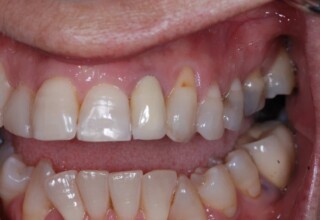

Restoration of bilateral diastemas between central and lateral incisors.

Diastemas were created mainly because of narrow laterals. After orthodontic treatment was finalized, the diastemas were closed with two composite resin restorations.